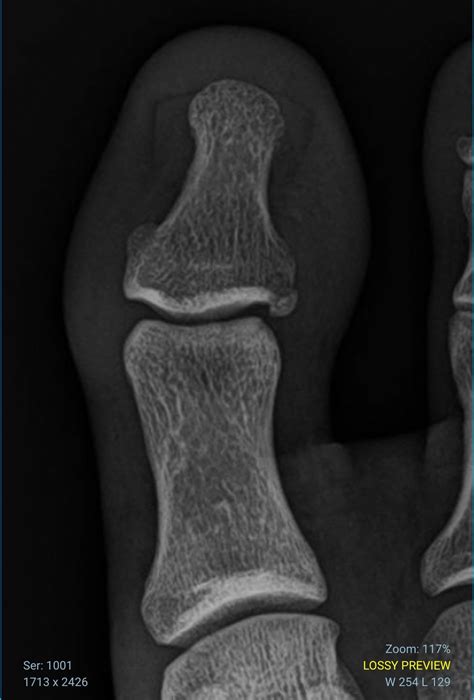

Your doctor will likely order an X-ray to determine the severity and location of the break. Treatment options will vary based on the findings:

• Surgery: In rare cases where the bone is severely displaced or fragmented, or if the break involves the joint surface, surgical intervention with pins or screws may be necessary to realign the bone.